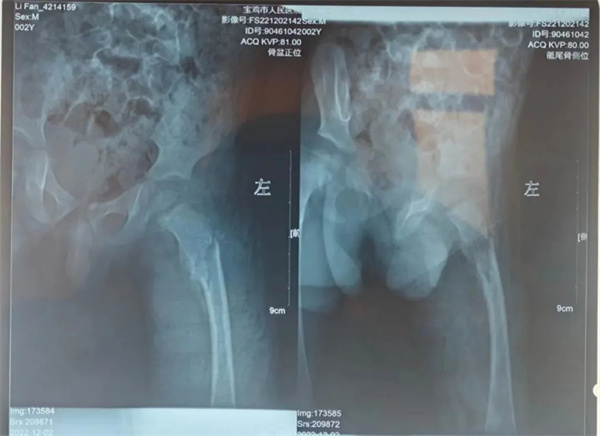

王文亮组织科室医生进行讨论研究后建议:如果选择手术治疗,有损伤骨骺可能,影响患儿骨骼发育,而且二期需要取除内固定装置,会给患儿造成较大的身体和心理创伤,家长不愿接受;而选择手法复位治疗的话,凭借小儿自身强大塑型能力,可以达到相当好的治疗效果。但压力就给到医生这边,因为复位后随时都有再次移位的可能。经王文亮与孩子父母亲反复沟通后分析利弊后,决定为患儿进行手法复位。在麻醉手术科全力配合下骨一科团队急诊为患儿实施全麻下“左股骨粗隆下骨折闭合手法复位+髋人字石膏固定术”,术中透视见复位满意。

术后第三天

术后康复治疗期间,科室医护紧密关注患儿情况,从护理、搬动、大小便等方面全方位照顾,防止骨折移位。因为患儿年幼,护士长王艳和主管护士雷晓玲时常来观察、安抚。雷晓玲观察到患儿每次看到透视机器就会紧张、害怕,便为带来了自家孩子的玩具和零食来缓解患儿检查治疗过程中的恐惧心理。在科室医护的悉心治疗照料下,经过三周动态X线复查,患儿骨折端愈合良好,已经长出了骨痂,这就意味着孩子的骨头已经开始愈合了,家人也不用担心骨折处发生移位了。看着孩子一天天多起来的笑容,家属慢慢舒展开的眉头,这大概是科室医护历经三周的辛苦耕耘后最好的收获。